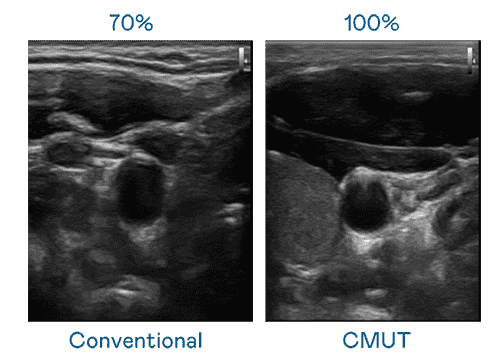

CMUT 技术是一种用电容式微机电元件来产生超音波讯号的技术。。与传统 PZT 压电式技术相比,,,,CMUT 频宽增加 30%,,,,更宽频的超音波讯号让影像解析度大幅提升,,,是实现高影像品质医疗超音波扫描、、、促进精准医疗发展的关键技术。。。

大频宽带来超清晰影像

超音波影像的解析度高低,,,,首先取决于探头能发出的讯号频宽。。。z6mg·人生就是博 CMUT 可提供高清晰的超音波讯号,,提供高频宽、、、高灵敏度、、、影像纹理细节更高的超音波影像,,,,协助医护人员缩短影像判读时间及利用精准的医疗影像进行诊断。。